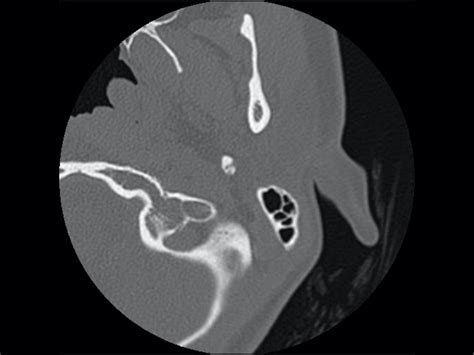

The Ct Temporal Bone scan is particularly useful in visualizing these intricate structures due to its high-resolution imaging capabilities. This makes it an invaluable tool for diagnosing various conditions affecting the temporal bone.

Imaging plays a crucial role in the diagnosis of temporal bone pathologies. The Ct Temporal Bone scan is the gold standard for evaluating the temporal bone due to its ability to provide detailed images of the bone's fine structures. Here are some key points about the diagnostic approach:

• High-Resolution CT: This technique uses thin slices to capture detailed images of the temporal bone. It is particularly useful for evaluating the bony structures and detecting fractures or erosions.

Ct Temporal Bone scans are typically performed with the patient lying down, and the scan takes about 10-15 minutes. The images are then reviewed by a radiologist who looks for any abnormalities in the temporal bone structures.

Interpreting Ct Temporal Bone scans requires a keen eye for detail and a thorough understanding of the temporal bone's anatomy. Here are some key points to consider when interpreting these scans: